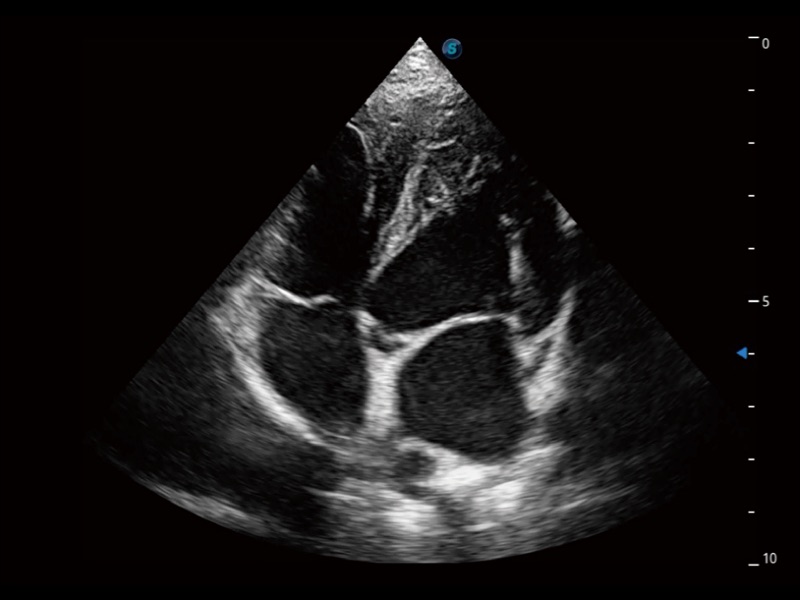

实时用颜色表示心肌组织运动,观察和定量组织的运动情况,对快速检测与评估心肌的灌注和活性、电传导及心肌收缩和舒张功能等均能提供重要的诊断信息。

ProPet 70专为动物医生设计,对不同的动物体型和生理结构作出了针对性的优化。通过动物影像专用软件,可满足个性化的应用需求,帮助动物医生获得更精确的诊断数据。